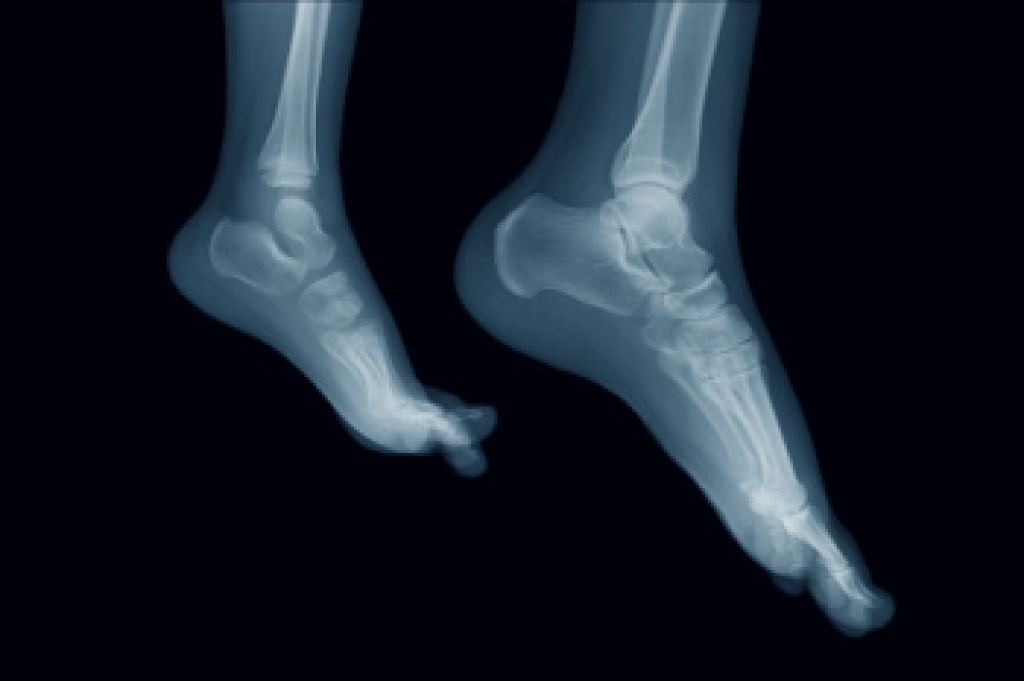

Persistent foot pain can be difficult to evaluate when symptoms do not clearly point to one cause. Imaging studies help clarify what is happening internally and support accurate care decisions. The process often begins with standard radiographs, which can identify alignment issues, joint changes, arthritis, and signs of repetitive stress. When those images do not fully explain symptoms, advanced imaging may be considered. Magnetic resonance imaging offers detailed views of muscles, tendons, ligaments, and other soft tissues, making it helpful when findings are unclear. Computed tomography provides sharp detail of bone structure and is useful for stress fractures, joint disease, and congenital connections between bones. In certain situations, nuclear imaging or diagnostic ultrasound can further pinpoint inflammation, injury, or altered tissue behavior. If foot pain persists, it is suggested that you see a podiatrist for an accurate diagnosis and appropriate treatment.

To figure out the cause of foot pain, podiatrists utilize several different methods. This can range from simple visual inspections and sensation tests to X-rays and MRI scans. Prior medical history, family medical history, and any recent physical traumatic events will all be taken into consideration for a proper diagnosis.